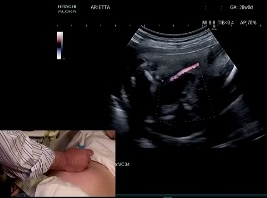

Examiner le tube digestif foetal

• Date : 20/06/2013